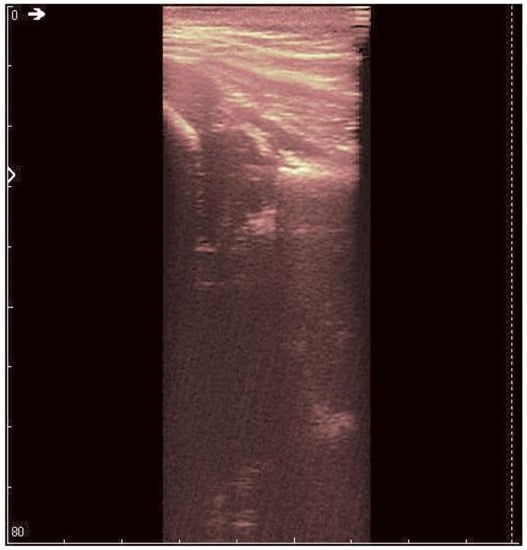

The original recording is displayed in Figure 3. As a first processing step, a color palette has been added to the original ultrasound in order to better highlight the noise and noise-free zones (Figure 4). The wavelet-based filter, as described in Section 2, is applied, and the processed image is shown in Figure 5.

Figure 3. Original recorded data.